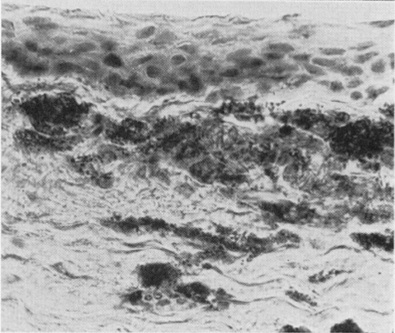

Des expériences de kératopathie induite expérimentalement chez les

lapins ont montré que les cellules endothéliales, les péricytes et les

kératinocytes absorbent des quantités accrues de cholestérol LDL et d’esters

de cholestérols. Le métabolisme cellulaire est incapable de métaboliser ces

grandes quantités de lipides et les cellules meurent, permettant le dépôt de

lipides et de protéines au sein du stroma de la cornée. Les macrophages,

cellules du système immun, tente de phagocyter les lipides et entraîne

l’apparition d’amas de cellules spumeuses.